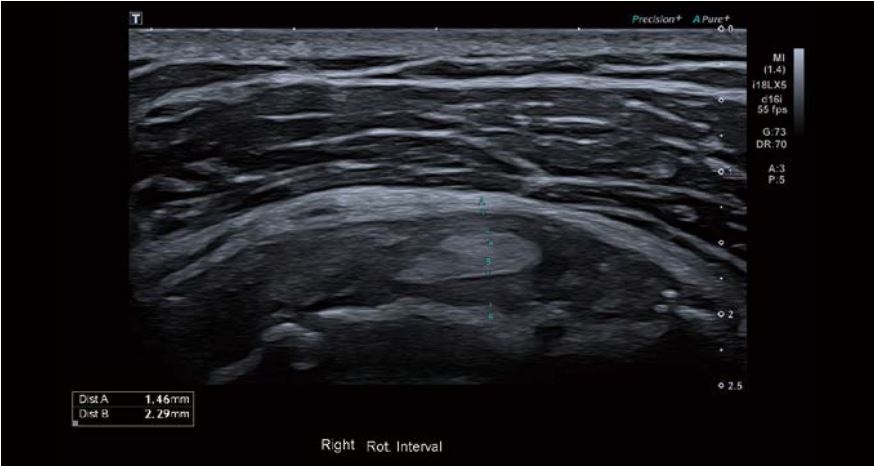

Було виявлено невеликий набряк оболонки сухожилля малого біцепса, потовщення та помірну васкуляризацію проміжку обертальної манжети. Спостерігалося незначне потовщення та асиметрія правої нижньої плечової зв'язки (НПЗ) та підпахвинної западини порівняно з лівою стороною. Товщина суглобової сумки була в межах норми, а в сухожиллях обертальної манжети спостерігалися мінімальні вікові зміни.

Зображення 3 Видно потовщення ділянки обертальної манжети, а режим Superb Micro-vascular Imaging (SMI) демонструє наявність судин